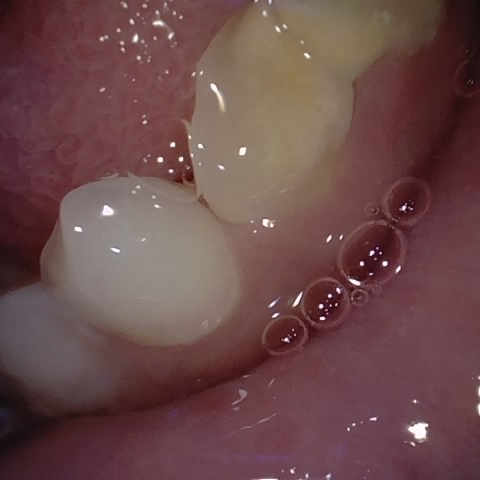

Annotated as "Bad"

Original Image Rendering Image